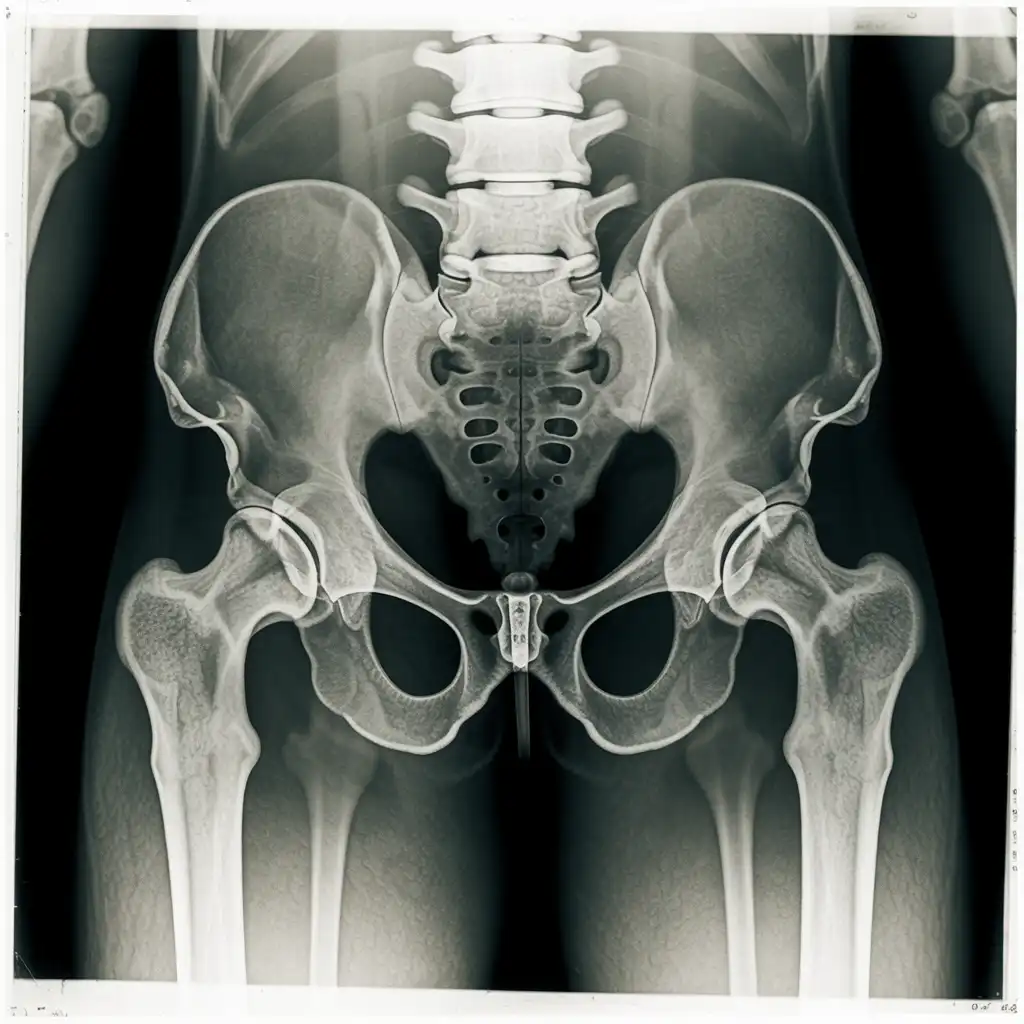

Il professionista entra con apparecchiature a basso dosaggio e schermi protettivi: bastano 2 × 2 m di spazio vicino al letto o alla poltrona. In pochi minuti acquisisce immagini HD, proprio come in un reparto ospedaliero.

Le immagini (formato DICOM) vengono caricate su un server crittografato e inviate immediatamente al radiologo. Se servono scatti aggiuntivi, il tecnico resta in collegamento video per eseguirli al volo.

Il medico radiologo analizza le immagini e firma il referto digitale all’istante. Ricevi il referto cartaceo e le immagini su chiavetta USB consegnati direttamente a casa tua subito dopo l'esame.

Usiamo le stesse apparecchiature certificate CE dei reparti ospedalieri, calibrate regolarmente. I referti sono validi per visite specialistiche, pronto soccorso e pratiche assicurative, e restano archiviati per 10 anni per ogni esigenza futura.